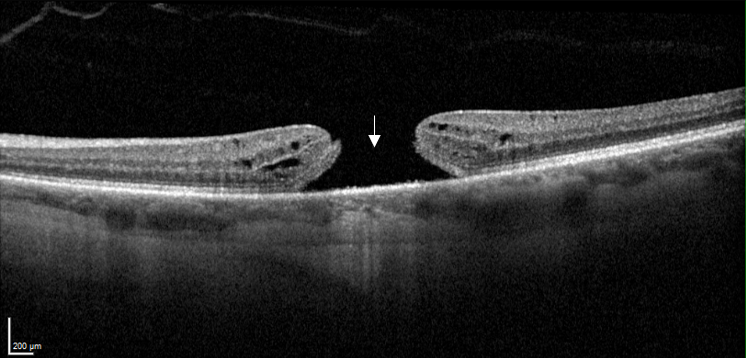

Coupe maculaire en OCT avant opération du trou maculaire : interruption de la rétine (flèche)